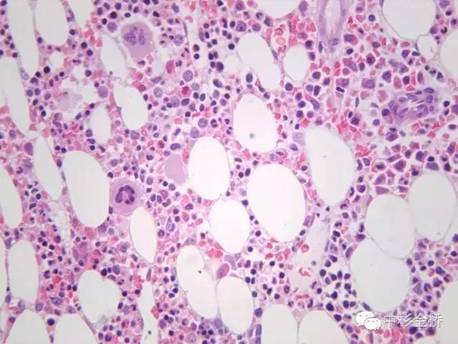

Rapidcal.Immuno脫鈣處理的骨髓標本,易于2?m連續(xù)完整切片,鏡下結(jié)構(gòu)清晰,細胞核與漿顏色鮮艷;常規(guī)硝酸脫鈣的骨髓標本,鏡下細胞核與漿顏色對比不明顯,染色質(zhì)不清晰。免疫組化實驗中,Rapidcal.Immuno脫鈣處理的骨髓標本,CD3、CD4、CD79a、CD20所標記的T細胞和B細胞定位準確,陽性表達強,背景清晰。常規(guī)硝酸脫鈣的骨髓標本,抗原部分丟失,標記物陽性結(jié)果表達較弱,背景有部分非特異性著色。

HE好